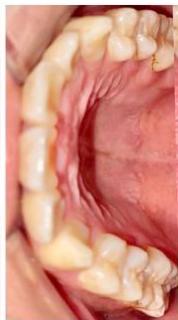

### b) Intraoral Examination

Intraoral examination revealed severe proclination and protrusion of both the maxillary and mandibular incisors [6]. The occlusal relationship was Class I at the canine (tooth 3) and first molar (tooth 6) levels bilaterally. A critical unfavorable biological factor was the proximity of the mandibular incisor roots to the labial cortical plate, representing a high-risk condition when planning extraction-based anterior retraction mechanics [10-12]. All four third molars were present.

Figure 2: Pre-Treatment Intraoral Photographs